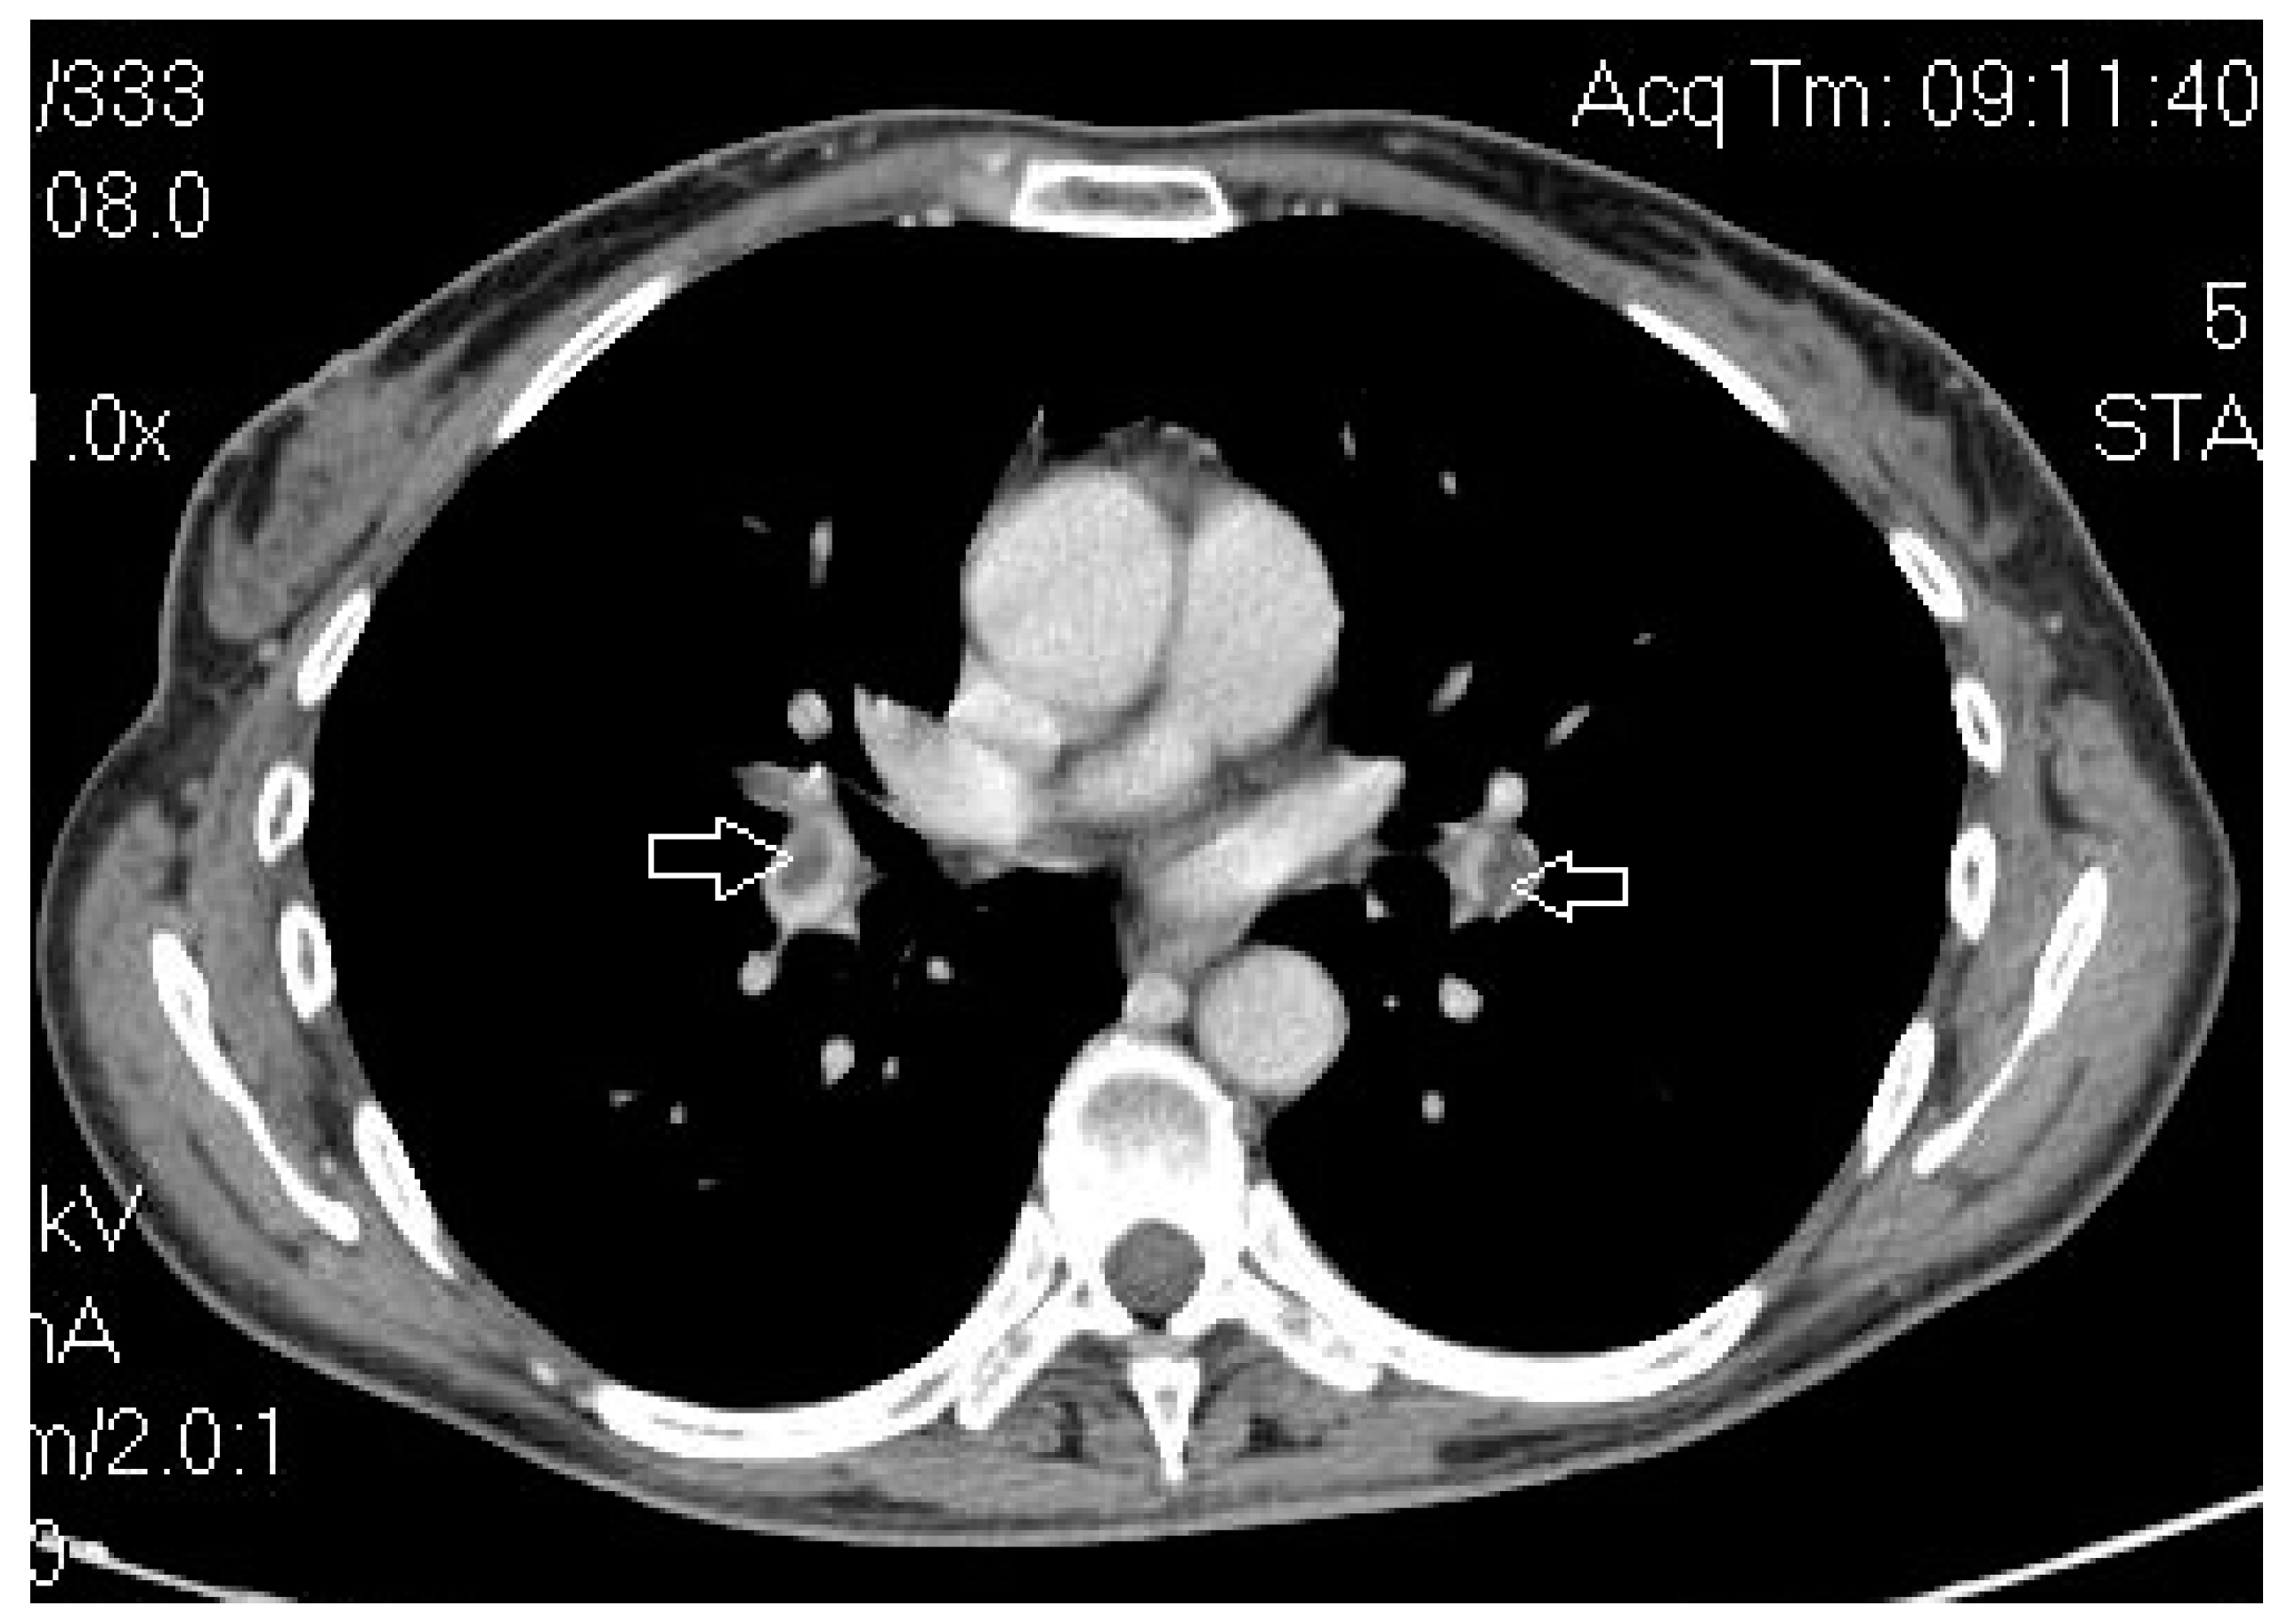

- Benoit, L.; Zerbib, J.; Koual, M.; Nguyen-Xuan, H.; Delanoy, N.; Le Frère-Belda, M.-A.; Bentivegna, E.; Bats, A.-S.; Fournier, L.; Azaïs, H. What Can We Learn from the 10 Mm Lymph Node Size Cut-off on the CT in Advanced Ovarian Cancer at the Time of Interval Debulking Surgery? Gynecol. Oncol. 2021, 162, 667–673. [Google Scholar] [CrossRef] [PubMed]